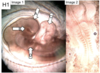

Name the following structures in the pictures below:

A. Name the sac like structure

B. Name the circular structure

C. Name the looped sac

D. Name the small slits

E.) Is the embryo on the right older of younger, provide reasoning

A. Mesencephalon (midbrain)

B. Optic vesicle/cup

C. Heart/Ventricle

D. Brachial arches

E) Younger (not as curled)